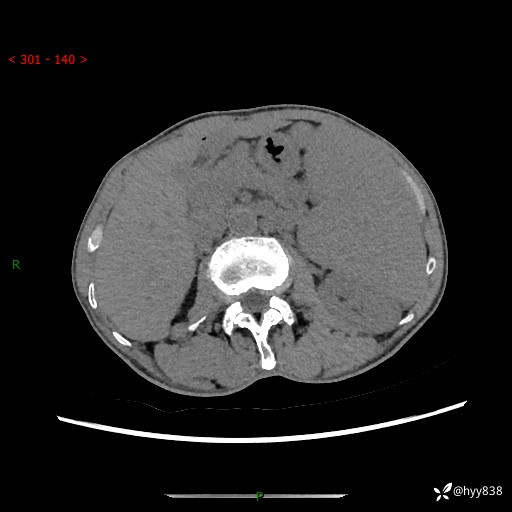

老年男性,脾大并脾脏弥漫粟粒状低密度,淋巴瘤 VS 肉芽肿 VS 血管瘤---结果公布

简要病史: 患者于3月前无明显诱因出现脾大,伴腹部轻微不适,具体不详,无腹痛、腹泻、腹胀,无头晕、头痛、乏力,无恶心、呕吐、呕血,无胸闷、气短、胸痛不适

上腹部CT平扫+增强